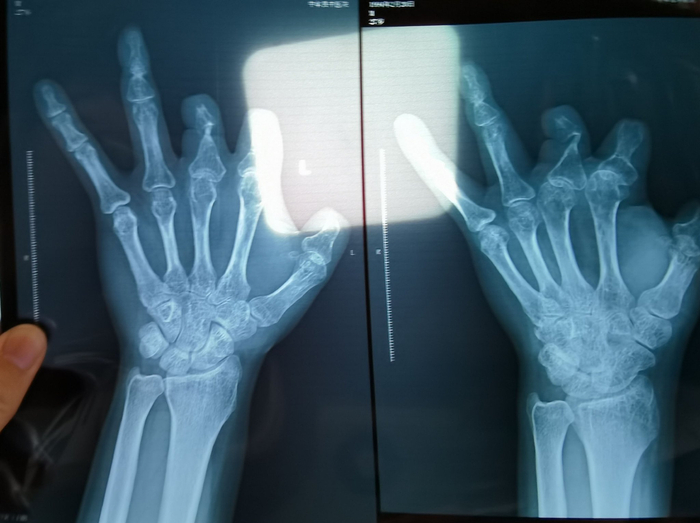

患者王海森左手拇指关节以上部位被电锯切断,收费单显示术中使用了微血管吻合装置,但X光片中未显示该器械。新京报记者 程亚龙 摄

该产品的代理商曾向新京报记者证实,微血管吻合装置为植入型医疗器材,患者拍摄X光片时会有显示。新京报记者获取了一位曾在郑大一附院接受手术、使用了该产品的患者的X光片,其手术部位可见一绿豆大小的光圈。

单价1.68万元,声称在术中植入体内、用于缝合血管的两个环形吻合装置,竟然在王海森的X光片上消失了。

装置上带有不锈钢针,不可能被人体吸收,唯一的可能就是“手术时其实没有使用”。尽管之前也有其他人向王海森透露过这一点,但直到看到片子前,他一直都不相信。

彭先生称,因为他的手术并不成功,术后他委托律师欲将郑大一附院诉至法庭。在律师的指导下,他到医院拍摄了X光片,偶然发现术中使用的6个吻合装置,都“消失”在了血管内。

王海森称,他出院约1年后,有人曾找到他说,这个价格昂贵的进口器材,并没有在手术中使用。当时他没有相信,直到2021年12月,经人提醒,王海森在老家开封尉氏县人民医院拍摄了左手X光片,才确认手术部位的确没有微血管吻合装置。2021年12月底,王海森向郑州市公安局二七分局刑侦大队报案。